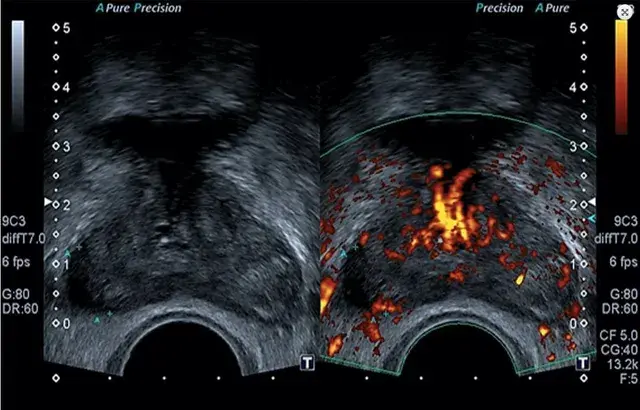

Próstata (guiada por ecografía transrectal)

Muestra de tejido prostático con aguja guiada por ultrasonido para detectar cáncer u otras patologías.